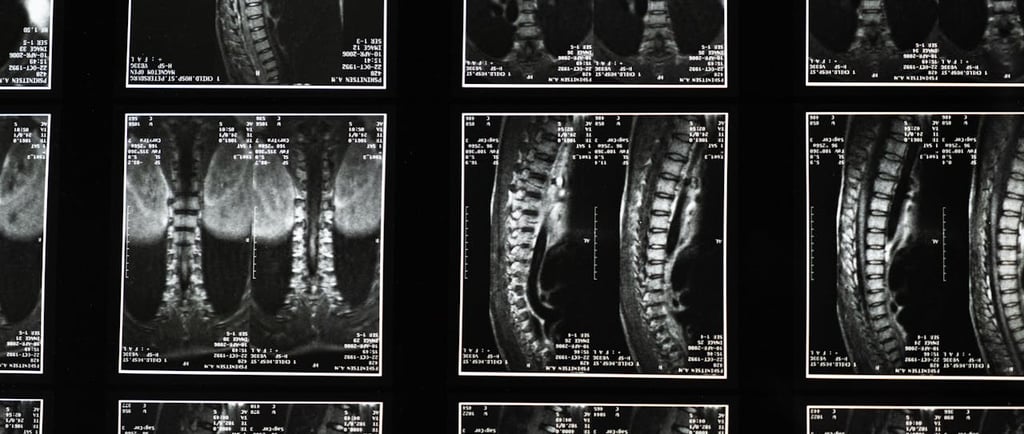

L’IRM lombaire (Imagerie par Résonance Magnétique) est un examen médical permettant d’explorer en détail la colonne vertébrale, les disques intervertébraux et les racines nerveuses. Cet examen est souvent demandé lorsqu’un patient présente une lombalgie persistante, une sciatique ou une suspicion de hernie discale lombaire.

Que montre une IRM lombaire ?

L’IRM lombaire permet d’observer avec précision :

les disques intervertébraux

les racines nerveuses

la moelle épinière

les articulations de la colonne vertébrale.

Cet examen est particulièrement utile pour diagnostiquer :

une hernie discale

un canal lombaire étroit

certaines pathologies inflammatoires ou dégénératives de la colonne vertébrale.